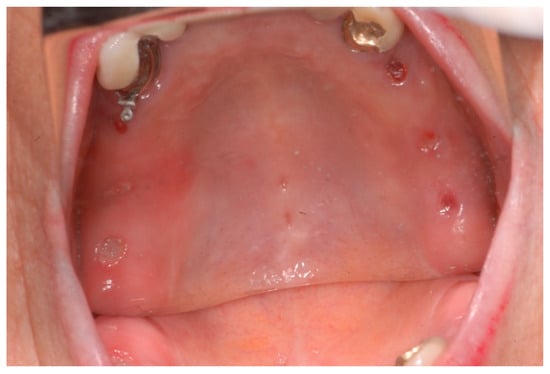

2.6. Case Study